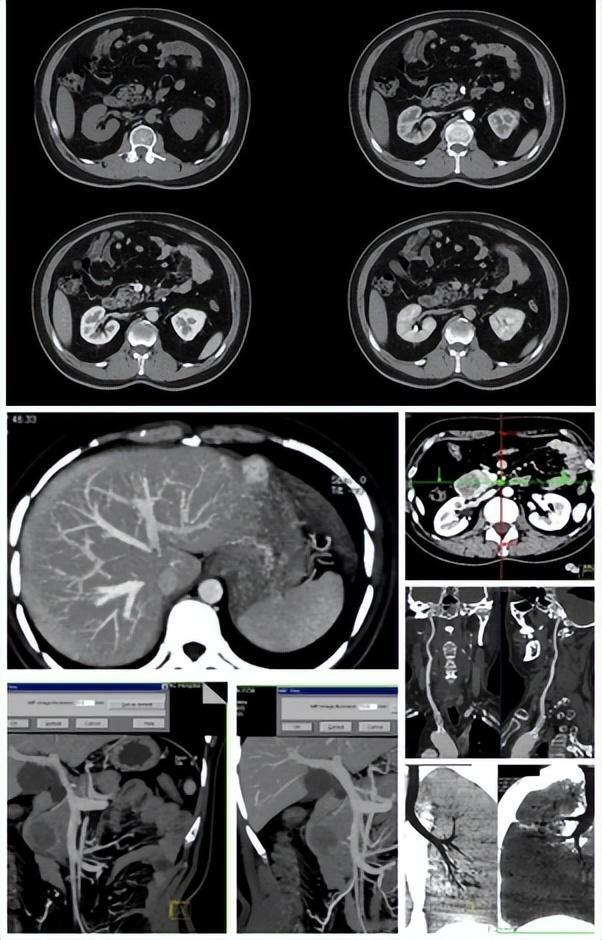

02CT (電子計算機體層攝影)

用X射線束對人體某部位一定厚度地掃描,根據人體不同組織對X線的吸收與透過率的不同,應用靈敏度極高的儀器對人體進行測量,然後將測量所獲取的數據輸入電子計算機,電子計算機對數據進行處理後,就可獲取人體被檢查部位的斷面或立體的圖像,發現體內任何部位的細小病變。它是通過數據計算得到的重建圖像。

雖然CT依舊用的是X射線,但不同於X光用的是X射線的螢光作用直接在攝影膠片或螢屏成像,CT則是通過數據計算得到的重建圖像。X線與CT檢查均有輻射!